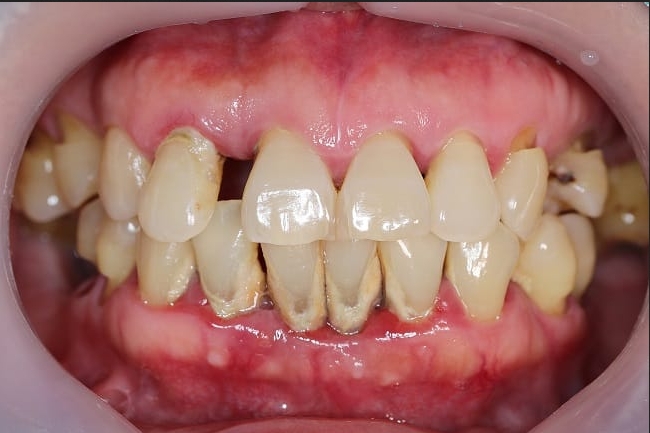

Periodontitis adalah infeksi gusi yang menyerang jaringan lunak dan tulang penyangga gigi. Kondisi ini perlu segera diobati agar tidak menimbulkan kerusakan permanen pada gigi dan jaringan sekitarnya.

Periodontitis merupakan komplikasi dari radang gusi (gingivitis) yang tidak ditangani. Jika berlangsung lama, kondisi ini dapat merusak jaringan di sekitar gusi dan gigi hingga menyebabkan gigi tanggal. Pada kasus yang parah, periodontitis juga dapat menimbulkan abses atau kumpulan nanah di gigi.

Bakteri pada karang gigi menghasilkan racun yang dapat memicu peradangan pada gusi (gingiva). Jika dibiarkan, radang gusi membuat terbentuknya celah antara gigi dan gusi, sehingga bakteri dapat masuk lebih dalam, merusak jaringan, dan bahkan tulang penyangga gigi.

Lama-kelamaan, kondisi tersebut dapat menyebabkan gigi goyang dan akhirnya tanggal. Pada kasus berat, periodontitis juga dapat menimbulkan abses atau timbunan nanah di sekitar gigi.

Gejala periodontitis bisa beragam dan tergantung pada perkembangan peradangan yang terjadi gusi dan gigi. Namun, ada beberapa gejala atau keluhan yang umum dialami oleh penderita periodontitis, yaitu: